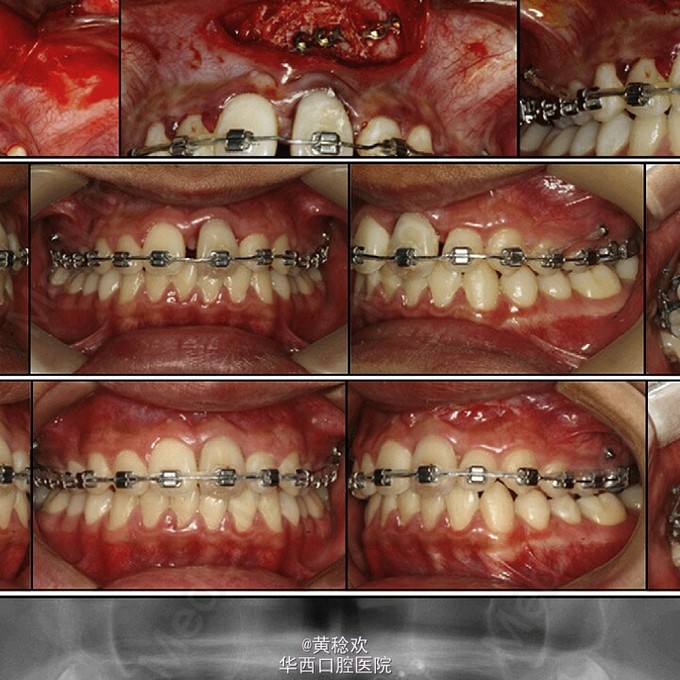

牙齿脱位对牙周膜、牙槽骨、牙龈、牙髓和牙骨质造成严重损害。脱位牙再植后经常伴有牙骨粘连等并发症。牙骨粘连指的是局部牙骨质和周围牙槽骨融合,多起因为牙齿正在萌出过程中或萌出后受到机械性、温度或者代谢产物刺激,对牙周膜造成损伤,好发于恒切牙。 牙骨粘连可通过临床和放射片检查诊断。临床检查包括低咬合状态、叩诊和松动度测试,最明显的特征是即便该牙施加正畸牵引力后也无法移动。整个牙的牙骨粘连可以通过放射片显示,其特征为无明显的牙周膜影响。但是如果该牙只有颊侧或者舌侧粘连,放射片上很难判断。近年来,CBCT的引入,可以逐渐将放射检查视野拓宽到3D层面,增强了对骨牙粘连的准确性。治疗骨牙粘连的方案包括:拔除、截冠、修复、手术半脱位、骨切开术和牵张成骨术等。